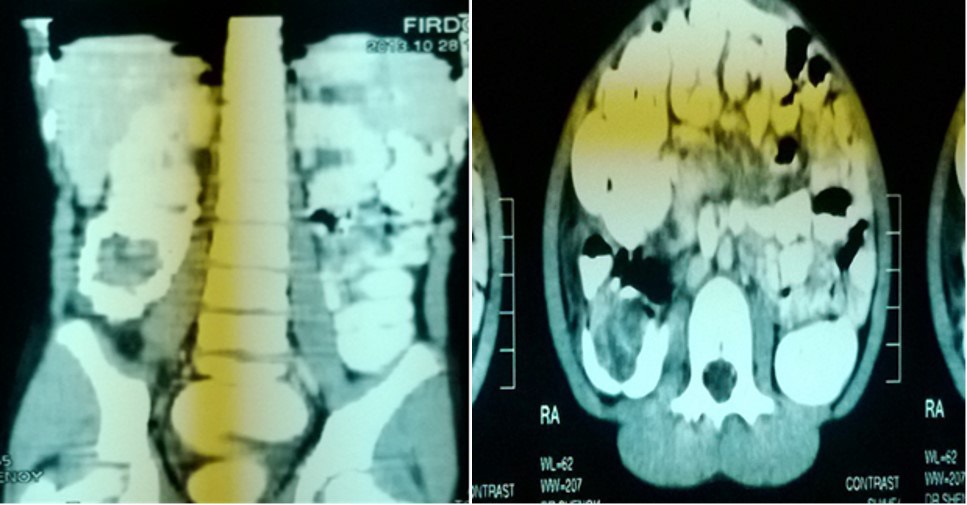

Computer tomograpahy:

• CT was done in 2 of our cases

• 1 case of PEUTZ JEGHERS SYNDROME

• 1 case was of chronic intussusception with benign polyp as lead point in ascending colon

Chronic intussusception:

• 12 years old female patient presented with chronic abdominal pain since 6 months.

• USG ABDOMEN-WNL.

• CT ABDOMEN.

• Abdominal CT scan

• Accuracy approaching 100%; especially good for lead points

• High cost, risk of radiation, and risk of sedation in children make it unpractical